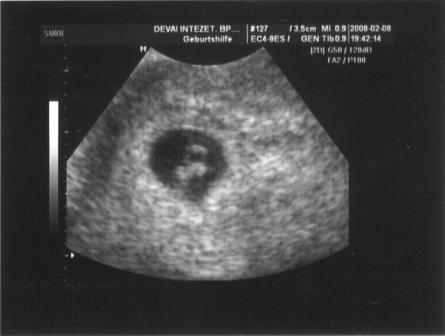

Az uh-n minden rendben volt, hallgattuk a szivhangot, vagy nem is tudom, szerintem az volt, hogy a köldökzsinórban keringett a vér és annak a hangja volt, a súlya 1262 g, szerintem az elég sok igy 28 hetesen, de nemtudom honnan tudnám ezt megnézni, meg farfekvéses még mindig a kincsem, de a doki azt mondta, hogy van még ideje megfordulni, remélem meg fog. Ééééééééééés a lényeg, hogy a doki szerint 100 %-ig biztos, hogy KISLÁNY! Hát nemtudom, én még mindig nem tudom elhinni, de kaptunk róla képet, majd otthon beszkennelem, és felteszem, hátha valaki ért hozzá?!